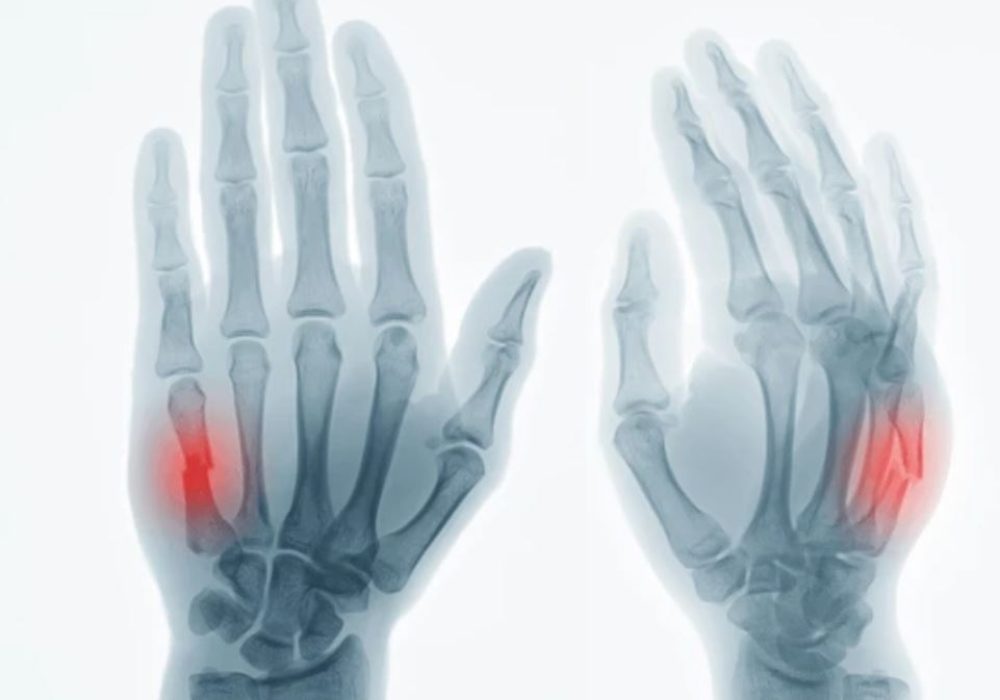

2 Metacarpal & Phalanx Fracture

A metacarpal fracture is a type of bone fracture (broken bone). Your metacarpals are the bones in your hand that connect your thumb and finger bones (your phalanges) to your wrist. You can feel your metacarpals by pressing on the back of your hand.

Your healthcare provider will diagnose a metacarpal fracture with a physical exam and imaging tests.

They’ll probably be able to feel or see a metacarpal fracture in your hand, but you’ll still need imaging tests to confirm which bones are broken and what type of fracture you have.

You’ll need at least one of a few imaging tests to take pictures of your fracture, such as: